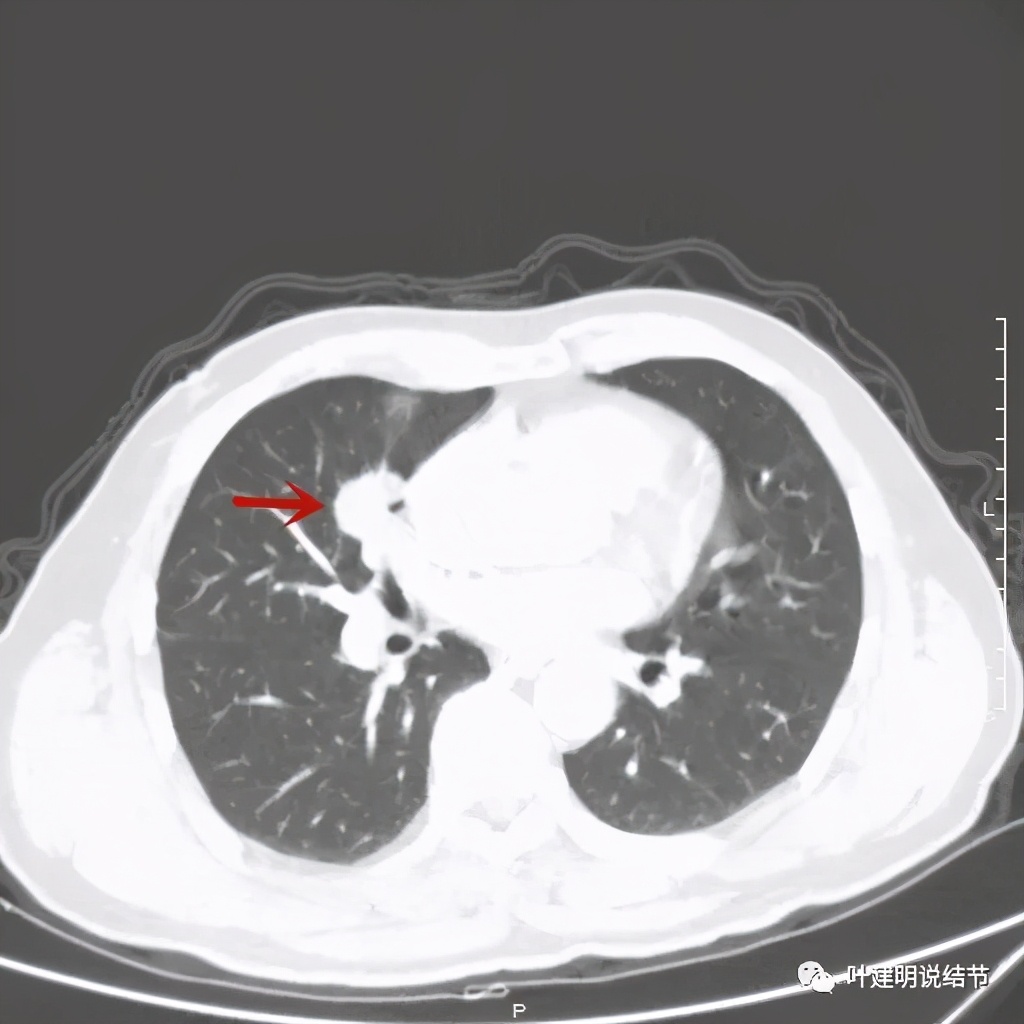

上图示病灶实性,且粉色箭头所示处边缘不平整,似细毛刺征(不太典型),蓝色箭头示像支气管截断(肿瘤堵塞的样子,但后文中有气管镜下未见异常,那么可能是角度的关系)

上图紫色箭头示浅分叶征明显,红色箭头示病灶牵拉胸膜(纵隔侧的胸膜)

上图绿色箭头示支气管通气征